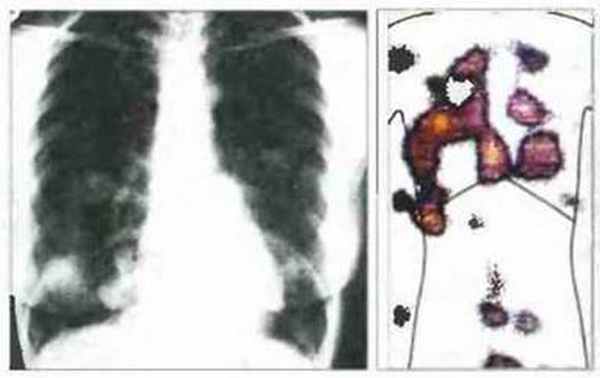

In vivo. Для выявления опухолей in vivo используют радиоактивно меченные антитела к опухолеассоциированным антигенам (рис. 20.14), однако этот метол часто менее чувствительней, чем современные методы компьютерной томографии или ядерного магнитного резонанса. Кроме того, иммуносцинтиграфия имеет те недостатки, что используемые антитела необходимо заново метить при исследовании каждого больного и для определения различных типов опухолей оптимальны различные антитела. Чувствительность иммуносцинтиграфии в будущем может быть повышена за счет получения рекомбинантных фрагментов высокоаффинных антител.

Рис. 20.14. Радиография грудной клетки и иммуносцинтиграфическое сканирование больного с карциномой толстой кишки и метастазами в легких и печени. Моноклональные антитела YPC2/12.1 к опухоли толстой кишки человека взаимодействуют с раково-эмбриональным антигеном (РЭА) (гликопротеин с мол. массой 180 кДа). Антитела радиоактивно метили 131 I и вводили внутривенно. Сцинтиграммы были получены через 48 ч. Изображение получено с исключением фонового окрашивания, обусловленного неспецифическим окрашиванием антител крови. (Фото любезно предоставлены проф. К. Sokora).